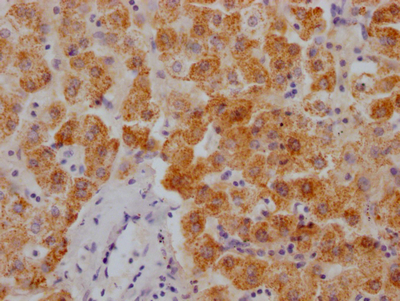

The image on the left is immunohistochemistry of paraffin-embedded Human gastic cancer tissue using CSB-PA196653(ABI1 Antibody) at dilution 1/40, on the right is treated with synthetic peptide. (Original magnification: ×200)